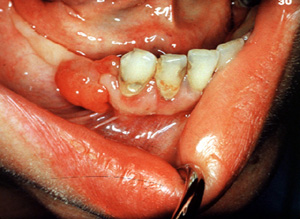

Aquí hay

otro ejemplo típico ocurriendo en el mucosa edéntula. Incluso la

irritación más ligera puede causarhemorragia. Un granulomapiógenopueden crecer rápidamente y pueden simular un tumor maligno;

obviamente, el diagnóstico preciso requiere de la biopsia.